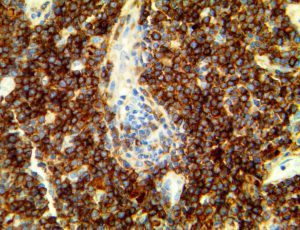

It is the ICU physician who is most likely to witness one of the deadliest manifestations of the abnormal immunological response, the cytokine storm syndrome (CSS). This response is also referred to by some as the cytokine release syndrome (CRS). CSS is characterized by continuous activation and expansion of macrophage and lymphocyte populations, which secrete large amounts of cytokines, causing the cytokine storm. This massive cytokine release is akin to hemophagocytic lymphohistiocytosis (HLH) disease, a syndrome characterized by initial unchecked and persistent activation of cytotoxic T lymphocytes and NK cells.

Clinical and laboratory manifestations of HLH include fever, enlarged liver and/or spleen, neurologic dysfunction, coagulopathy, liver dysfunction, cytopenias (i.e., low levels of erythrocytes, leukocytes, and/or platelets), hypertriglyceridemia, hyperferritinemia, hemophagocytosis, and eventually diminished NK cell activity as the immune system becomes progressively paralyzed. HLH can be familial (primary HLH) or secondary to another disease process (sHLH), such as rheumatic disease, in which it is referred to as macrophage activation syndrome (MAS, characterized by elevated ferritin).